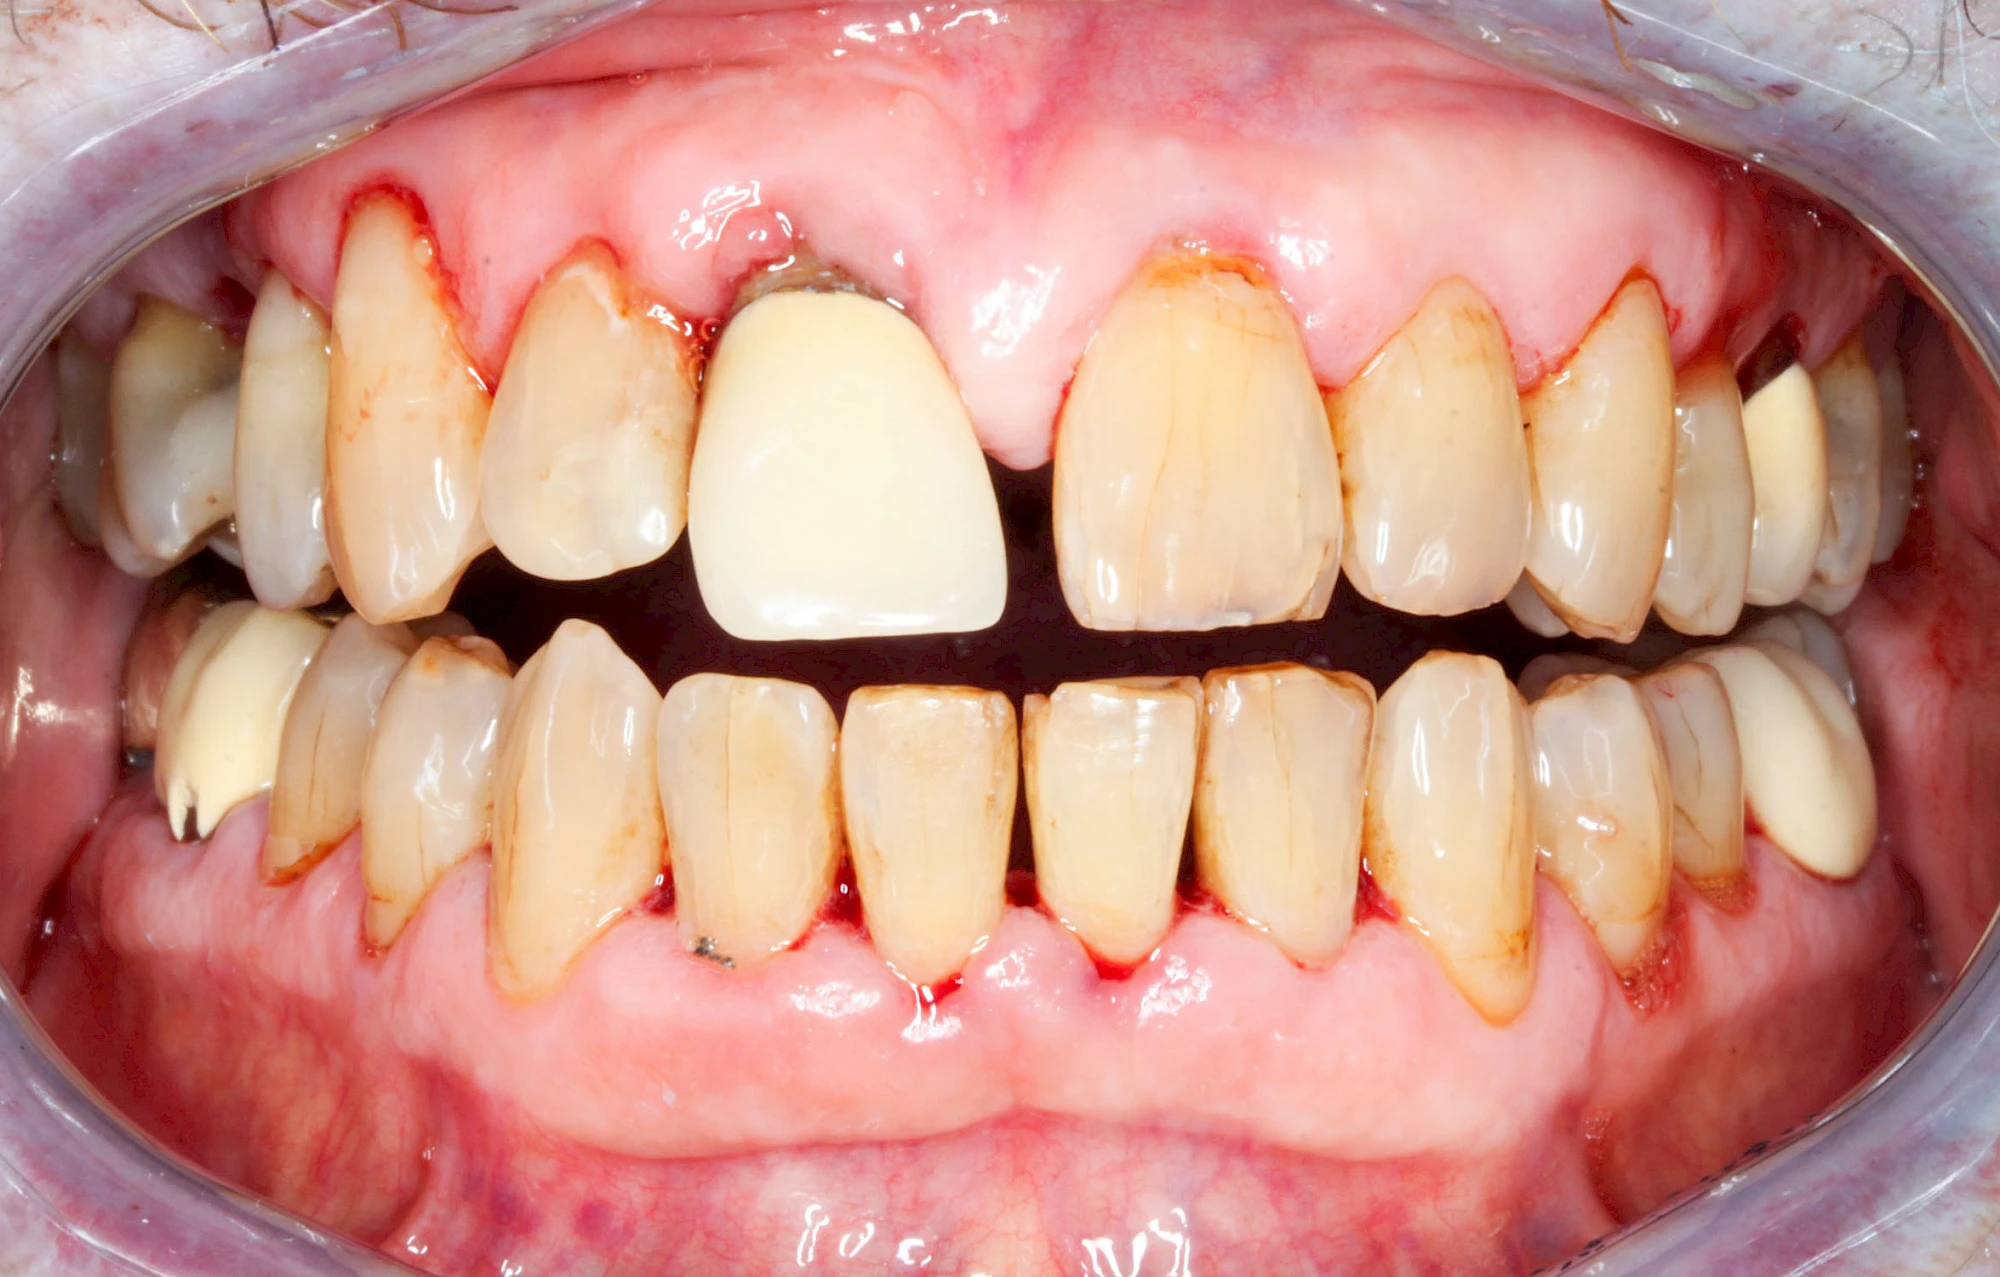

Gingivitis & Parodontitis: Stadien

Ist zunächst nur das Zahnfleisch von der Entzündung betroffen, spricht man von Gingivitis. Später, wenn auch der Knochen um die Zähne herum entzündet ist, spricht man von einer Parodontitis. Bei der Parodontitis wird der Knochen nach und nach abgebaut und das Zahnfleisch zieht sich zurück. Die Zahnhälse und Zahnwurzeloberflächen liegen mehr und mehr frei. Die Zähne werden zunehmend lockerer und fallen schließlich aus.

Umgekehrt hat eine Parodontitis vielfältige Auswirkungen auf die allgemeine Gesundheit.